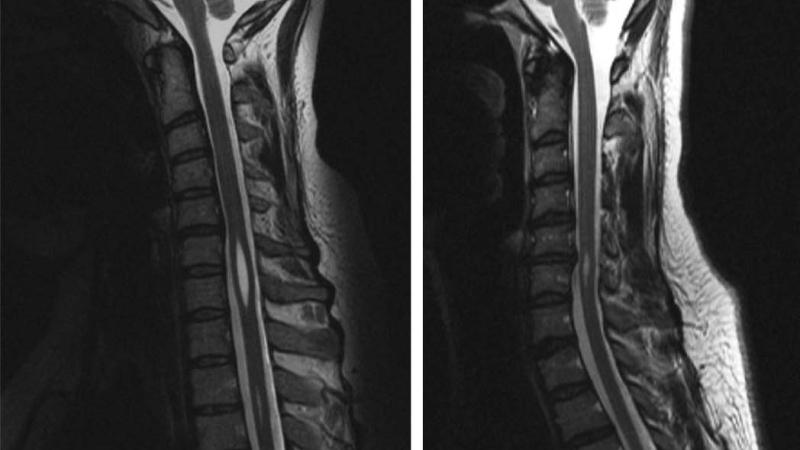

Для установления точного диагноза необходимо обратиться к врачу-неврологу. Этот специалист основывает свои выводы на данных, полученных с помощью компьютерной и магнитно-резонансной томографии. Исследованию могут подвергаться различные отделы позвоночника: грудной, шейный, а в редких случаях и поясничный.

Диагностика сирингомиелии обычно включает в себя магнитно-резонансную томографию (МРТ), которая позволяет визуализировать наличие кист в спинном мозге. Также могут быть проведены неврологические тесты для оценки функции нервной системы.